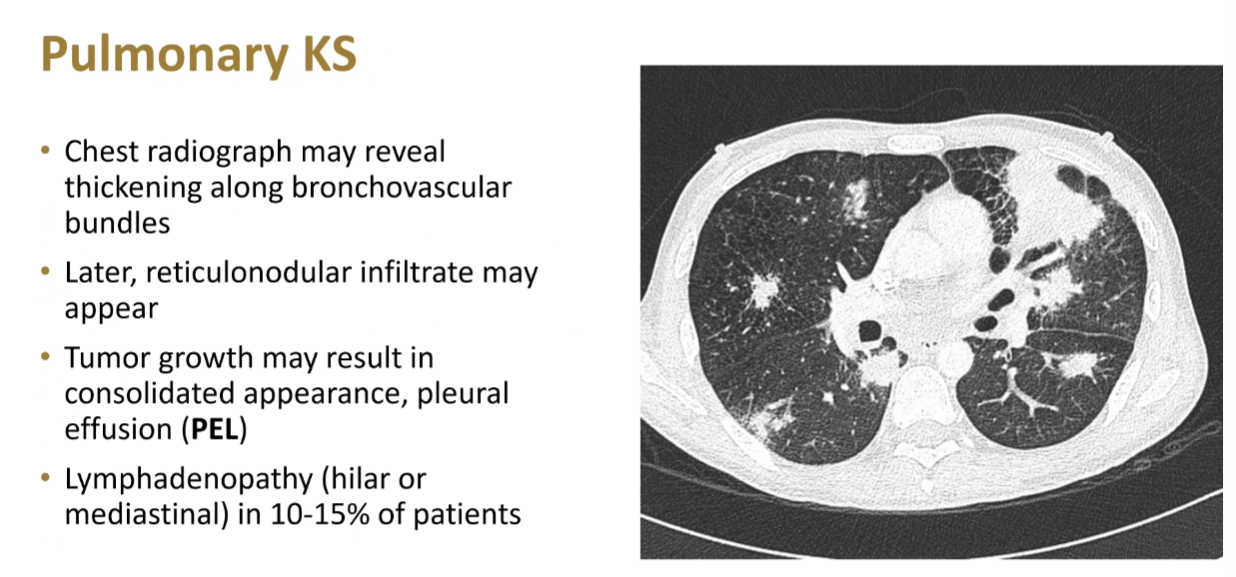

Kaposi Sarcoma related: HIV human immunodeficiency viruses tags: #literature #id rarer hemoptysis often cough/dyspnea actually less often canon ball lesions EBUS with high risk of bleed use BAL 1 Links to this note HIV human immunodeficiency viruses Kaposi Sarcoma Footnotes HIV talk with Maves ↩